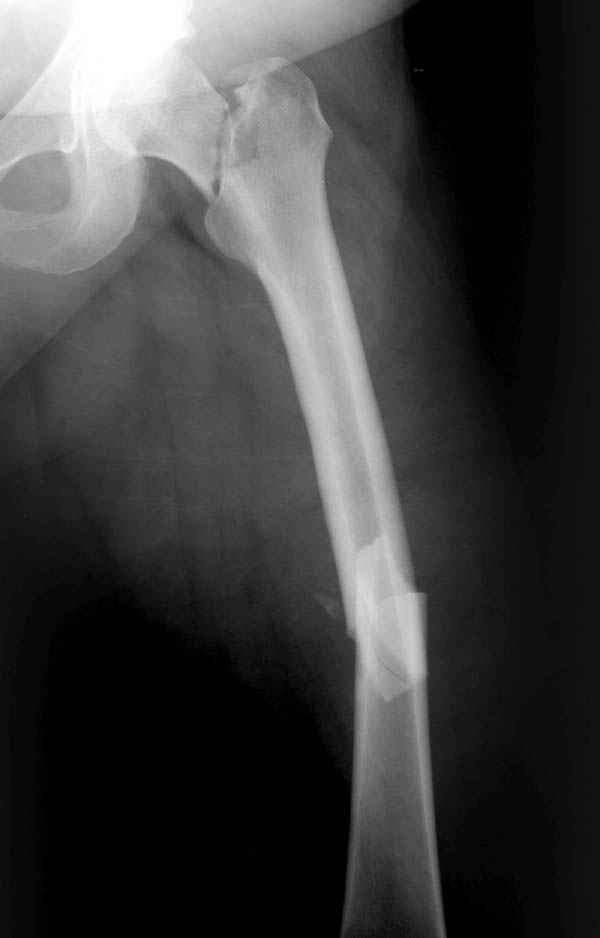

Ошибки случаются, когда игнорируются правила обследования больных с переломом бедра. Часто, когда "экономят" рентген пленки и снимают без надлежащих захватов сустава.

Одним из "золотых" правил при лечении переломов бедра в обязательном порядке до операции необходимо убедиться в отсутствии или наличии перелома шейки.

Отдельный снимок шейки или ЭОП является стандартом обследования. Все сомнительные рентген снимки проверяются тщательно дополнительными срезами КТ.

Из-за опасности вторичного смещения переломов "без смещения" во время интрамедуллярных манипуляций, особенно при ретроградном введении, необходимо каждый случай протоколировать с описанием состояния шейки после операции.

А не опорная болтающаяся конечность с большим рычагом усложнит состояние перелома шейки и поэтому ипсилатеральные переломы, тем более ятрогенные, очень часто осложняются двойными ложными суставами.

Учитывая молодой возраст больного, из всех рекомендуемых вариантов для лечения ложного сустава шейки предпочтительным является вальгусная остеотомия (на сайте имеются прежние разборы) из-за простоты исполнения и биомехнических преимуществ.

После удаления штифта нет необходимости проведения "стресса" на сращение, лучше провести фиксацию пластиной по два шурупа с каждой стороны.

Минимальный перкутанный доступ без ущерба сохранит сомнительное мозолеобразование и создаст условия для профилактики ложного сустава бедра.

Или при наличии ретроградной техники, короткий штифт с одним блокирующим шурупом дистально, создаст адекватную фиксацию и условия для быстрейшего восстановления.